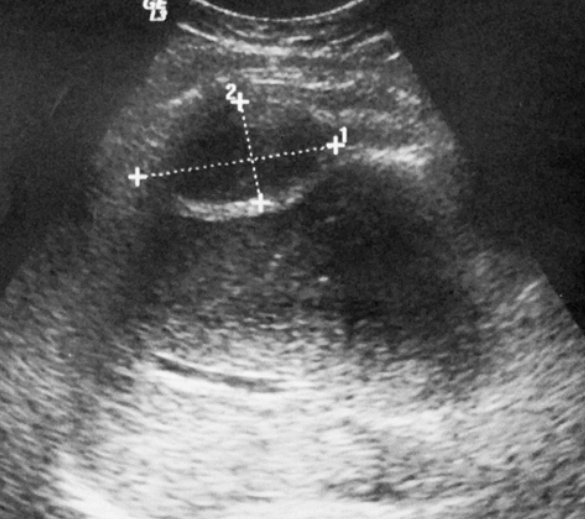

US finding

- 초음파영상에서 fluid-fluid level을 동반한 액체저류가 보인다.

- 낭종은 무에코가 아닌 내부에코를 동반한다.